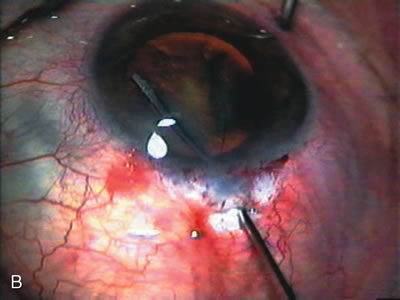

CASE 6: ANTICIPATED LENS EXTRACTION POST FAILED TRABECULECTOMY WITH ADVANCED DISC DAMAGE AND IOP OUTSIDE TARGET PRESSURE RANGE

The inflammation associated with lens extraction at any site usually causes complete failure of a marginal functioning bleb. In addition, pressure reduction by medical means is usually minimal in these recalcitrant cases, and combined surgery is indicated. In the past, these cases were approached with large-incision ECCE, clear corneal cataract incision, and bleb revision. Drawbacks included those mentioned earlier for large incision clear corneal cataract extraction, and bleb revision is often associated with conjunctival buttonholes, wound leaks, subconjunctival hematoma, destruction of friable sclera, and associated hypotony. With the advent of modern-day cataract surgery, a phacotrabeculectomy is often possible adjacent to the failed filter (Fig. 7). The ability to combine cataract extraction with implant and filtration surgery all through the same small incision has greatly improved outcomes for patients with marginal preoperative filters. There are several other viable options in this case. If the surgeon elects to remove the cataract through a temporal clear corneal incision, the bleb may be revised or a new adjacent filter fashioned. As mentioned earlier, revising a failed filter is technically challenging. If the surgeon believes it is not feasible to revise the filter or fashion a new one, a glaucoma drainage implant is a reasonable option combined with temporal lens extraction.172

Fig. 7. Phacotrabeculectomy adjacent to a failed filter in cataractous eye. The ability to combine small-incision cataract extraction with trabeculectomy all through the same incision adjacent to the failed filter allows the surgeon to work in a familiar superior area. Avoiding incisions into the existing bleb decreases conjunctival buttonholes, hypotony, operating room time, and subconjunctival bleeding. A. Appearance of failed bleb with exposure of superior temporal quadrant gained with a corneal traction suture. B. Prepare a limbus-based conjunctival flap and a scleral flap. C. This bleb is at high risk to fail again justifying the need for MMC, 0.2 mg/cc applied on a pledget for 4 minutes. D. Insert the keratome and perform phacotrabeculectomy in the usual fashion.